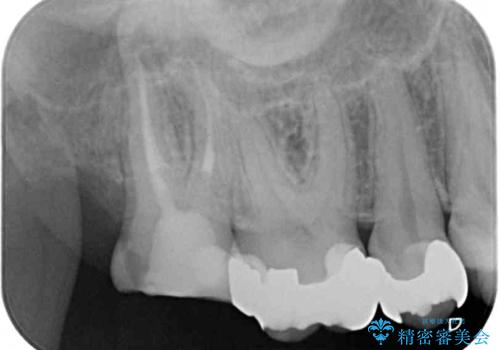

- 右上下の奥歯がむし歯でしみたり痛んだりするとのことで来院された患者様です。

下顎の奥歯は強い痛みを感じており、既に歯髄に不可逆的な炎症が起きていると診断されたため、根管治療の後にセラミッククラウンにて補綴治療を行うこととしました。

上顎の奥歯は最近銀歯による治療を行ったとのことでしたが、適合が不十分であり隙間からしみていたため、適合の良いゴールドインレーにて修復治療を行うこととしました。

下顎のむし歯は歯肉の中にまで及んでいたため、一部歯槽骨を削除し、歯肉縁上に健全歯質が位置するよう外科処置を併用しました。